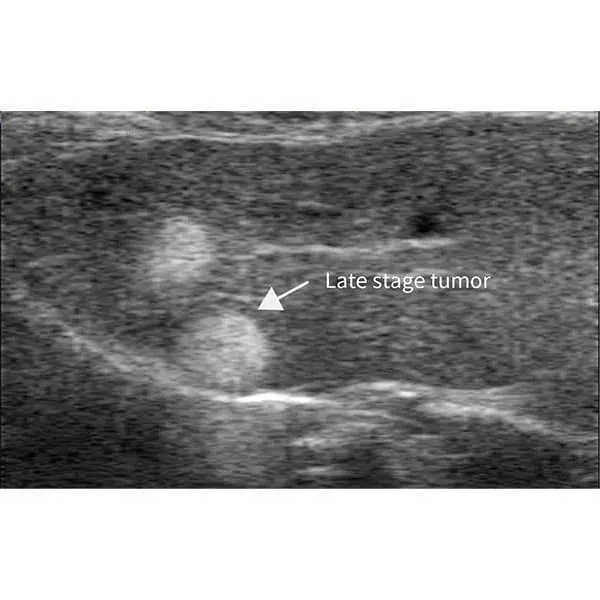

The RevoSilex F30/F60 delivers ultra-high-resolution, non-invasive imaging tailored for small animal models including mice, rabbits, and zebrafish. Equipped with advanced ultra-high-frequency technology and color Doppler functionality, it enables real-time assessment of cardiovascular performance, tumor vascularization, and physiological dynamics. Designed for applications in cardiovascular research, oncology, developmental biology, and drug discovery, its compact and portable architecture supports easy handling and reliable performance in longitudinal and repeat imaging studies.